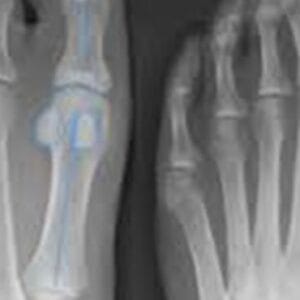

Foot & Ankle Patient informationArthritis refers to the inflammation of one or more joints, often leading to pain and stiffness. While it can affect any joint in the body, it is particularly common in the smaller joints of the foot and ankle, causing discomfort and limiting mobility. With over 100 types of arthritis identified,